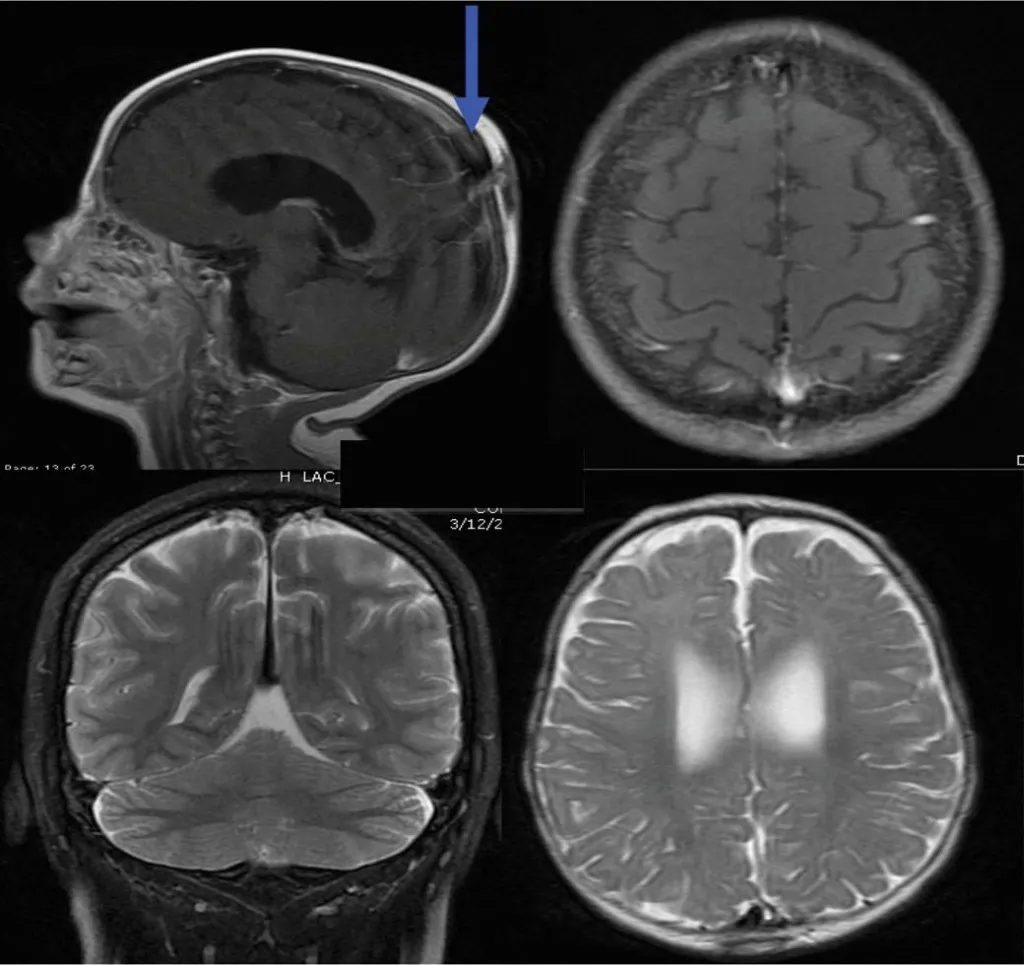

МРТ головного мозга, что позволяет выявить?

Что показывает МРТ головного мозга

Что скрывает МРТ головного мозга